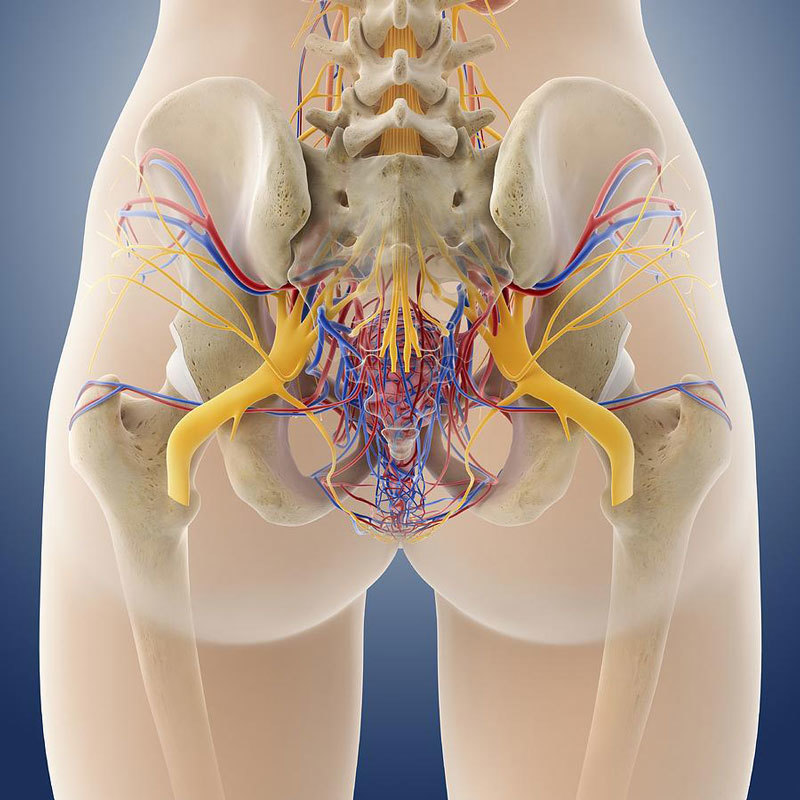

Боль в малом тазу у женщин: Причины и подходы к лечению